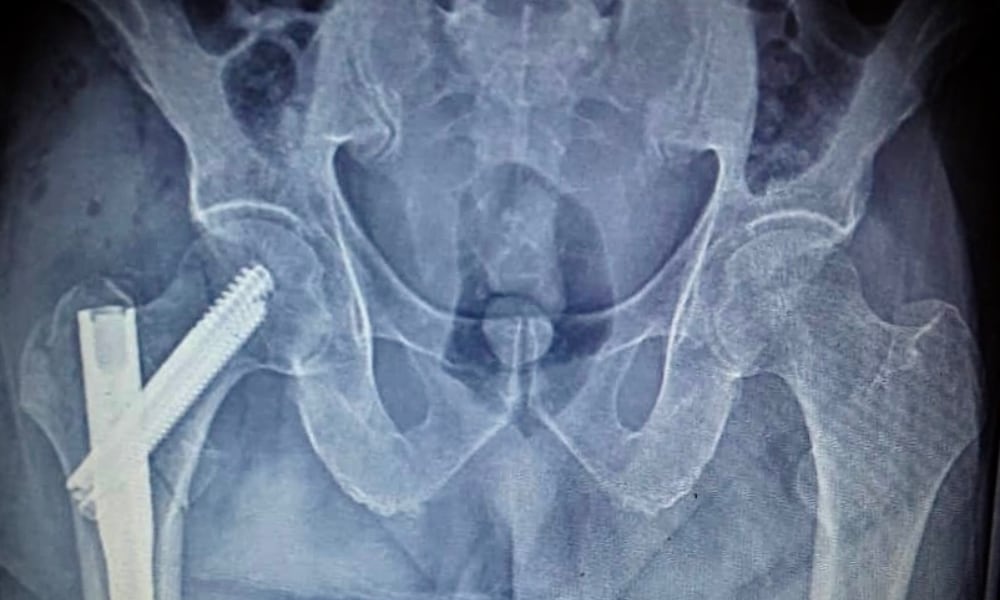

Femoral neck fractures consists 1% of all fractures. 80% of the fractures develop over 60 years of age. The prevalence is 4-5 folds more in women. Femoral neck fracture may develop as a consequence of accidental fall or hit on hip side.

The general condition of the patient is not much affected. There is pain on hip region in nondisplaced fractures. The pain emerges on hip when someone hits on ankle or greater trochanter. There is severe pain on displaced fractures and the patients cannot move their leg and the leg is on extroverted position. The diagnosis is made through X-rays. The impacted fractures in osteoporotic patients could be missed on X-rays therefore, computed tomography may be performed for diagnosis.

The recovery of femoral neck fractures is difficult. The circulation in femoral head is impacted due to fracture and femoral neck avascular necrosis may develop. Therefore, surgery is the only treatment option in all age groups. Hip compression nails are used in adults after femoral head partial prosthesis in elderly, and thin multiple nails(Knowles nails) are used for fixation in children to avoid serious damage on epiphysis plaque after anatomic reduction is performed in young patients. Although, the early mobilization and weight bearing are promoted after prosthesis operations, weight bearing after internal fixation operations must be allowed when the reunion is evident on radiologic images. The most important problem after femur fractures is the worsening of the general health in patients. Therefore, the surgery must be performed immediately and the patient must be mobilized shortly after the procedure. Otherwise, the patients may die due to heart and respiratory failures.